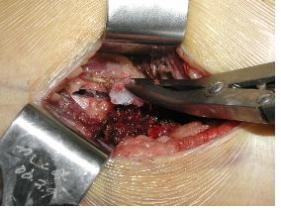

정확한 진단을 위해서는 조직검사가 필수적이며, 조직검사에는 천자검사법, 침 생검법과 수술을 하는 절개 생검법이 있습니다. 방사선검사나 자기공명영상(MRI)으로 어느 정도 예측은 가능하나 악성 골종양의 확실한 조직학적 진단을 위해서는 조직검사가 필요한 경우가 많습니다. 필요한 모든 다른 검사 후 진단의 최종 단계에 시행되는데, 이는 조직검사로 인해 종양 주위에 출혈이나 염증 등이 야기될 수 있어 방사선검사, 특히 자기공명영상(MRI) 검사에 지장을 주기 때문입니다. 조직검사의 방법과 위치는 나중에 시행될 사지 보존을 위한 수술적 치료를 생각하여 골종양 전문의에 의해 시행되어야 합니다.

시술 시 정확한 생검 부위를 선택하여 치료적 수술 시에 절제가 가능하도록 시행합니다. 출혈 부위, 궤양 형성 부위나 괴사 부위를 피하여 생검을 시행하여야 하는데, 종양 중심부에는 괴사가 많고 변연부에는 이차적 변화가 없는 종양조직이 있어 주의해야 합니다. 부위에 따라 종양의 분화도가 다를 수 있으므로 종양의 여러 부위에서 충분한 양의 조직을 채취합니다.

[ 절개 생검 ]